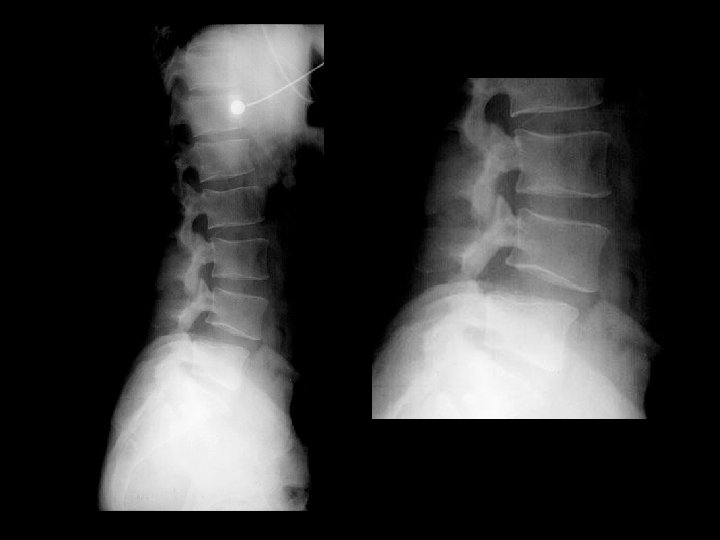

Ankylosing Spondylitis • • Findings: – fused SI joints – right hip erosions – lumbar syndesmophytes Sero-negative chronic inflammatory disease Starts in the low back and progesses upward ddx (sacroilitis) – bilateral • ank spond • IBD – Unilateral • Reiter’s • psoriasis